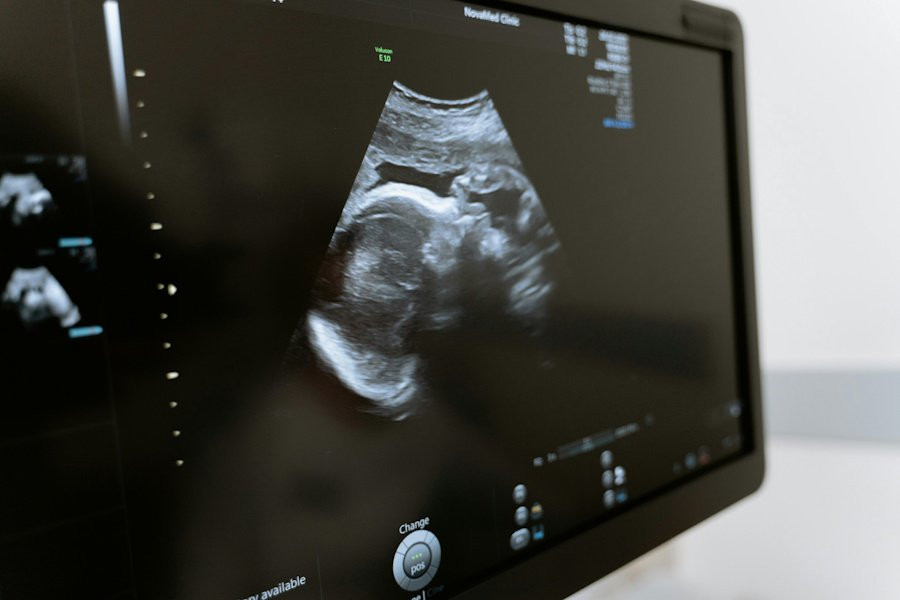

Суррогатное материнство связано с повышенным риском осложнений беременности

Ученые из McGill University (Канада) провели масштабное исследование, которое показало, что суррогатные матери сталкиваются со значительно более высоким риском серьезных осложнений во время беременности. Результаты работы были опубликованы в медицинском журнале Annals of Internal Medicine.

Эксперты изучили данные о 863 017 одноплодных родах, из которых 806 приходилось на гестационных носителей — так называют женщин, вынашивающих детей для других людей. Результаты исследования оказались тревожными: вероятность тяжелых материнских заболеваний среди суррогатных матерей составила 7,8%. Это более чем в три раза выше, чем у женщин, зачавших ребенка самостоятельно, и почти в два раза выше по сравнению с женщинами, прошедшими процедуру экстракорпорального оплодотворения (ЭКО).

Кроме того, исследователи отметили, что у детей, рожденных суррогатными матерями, был несколько выше риск тяжелых неонатальных заболеваний, связанных с преждевременными родами.

Эти данные подчеркивают важность тщательного медицинского наблюдения за суррогатными матерями в течение всей беременности и после родов.